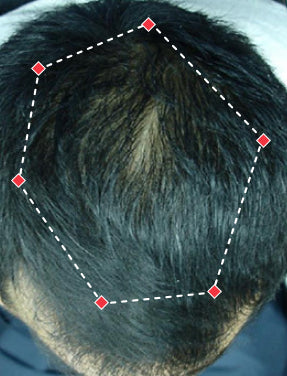

Indications for Use

The iRESTORE Hair Growth System Elite is indicated to promote hair growth in males who have Norwood-Hamilton Classifications of IIa to V and in females who have Ludwig-Savin Classifications I to II, and in both with Fitzpatrick Skin Phototypes I to IV. In other words, iRESTORE is not intended for people who are bald or have advanced hair loss.

Laser therapy works to reactivate thinning and dormant hairs. For completely bald areas of the scalp, there may be no way to promote hair regrowth. If you still have hair follicles, laser therapy may be beneficial to you.

Not sure? Email us to have our specialists evaluate your scalp conditions to see if iRESTORE is suitable for you.